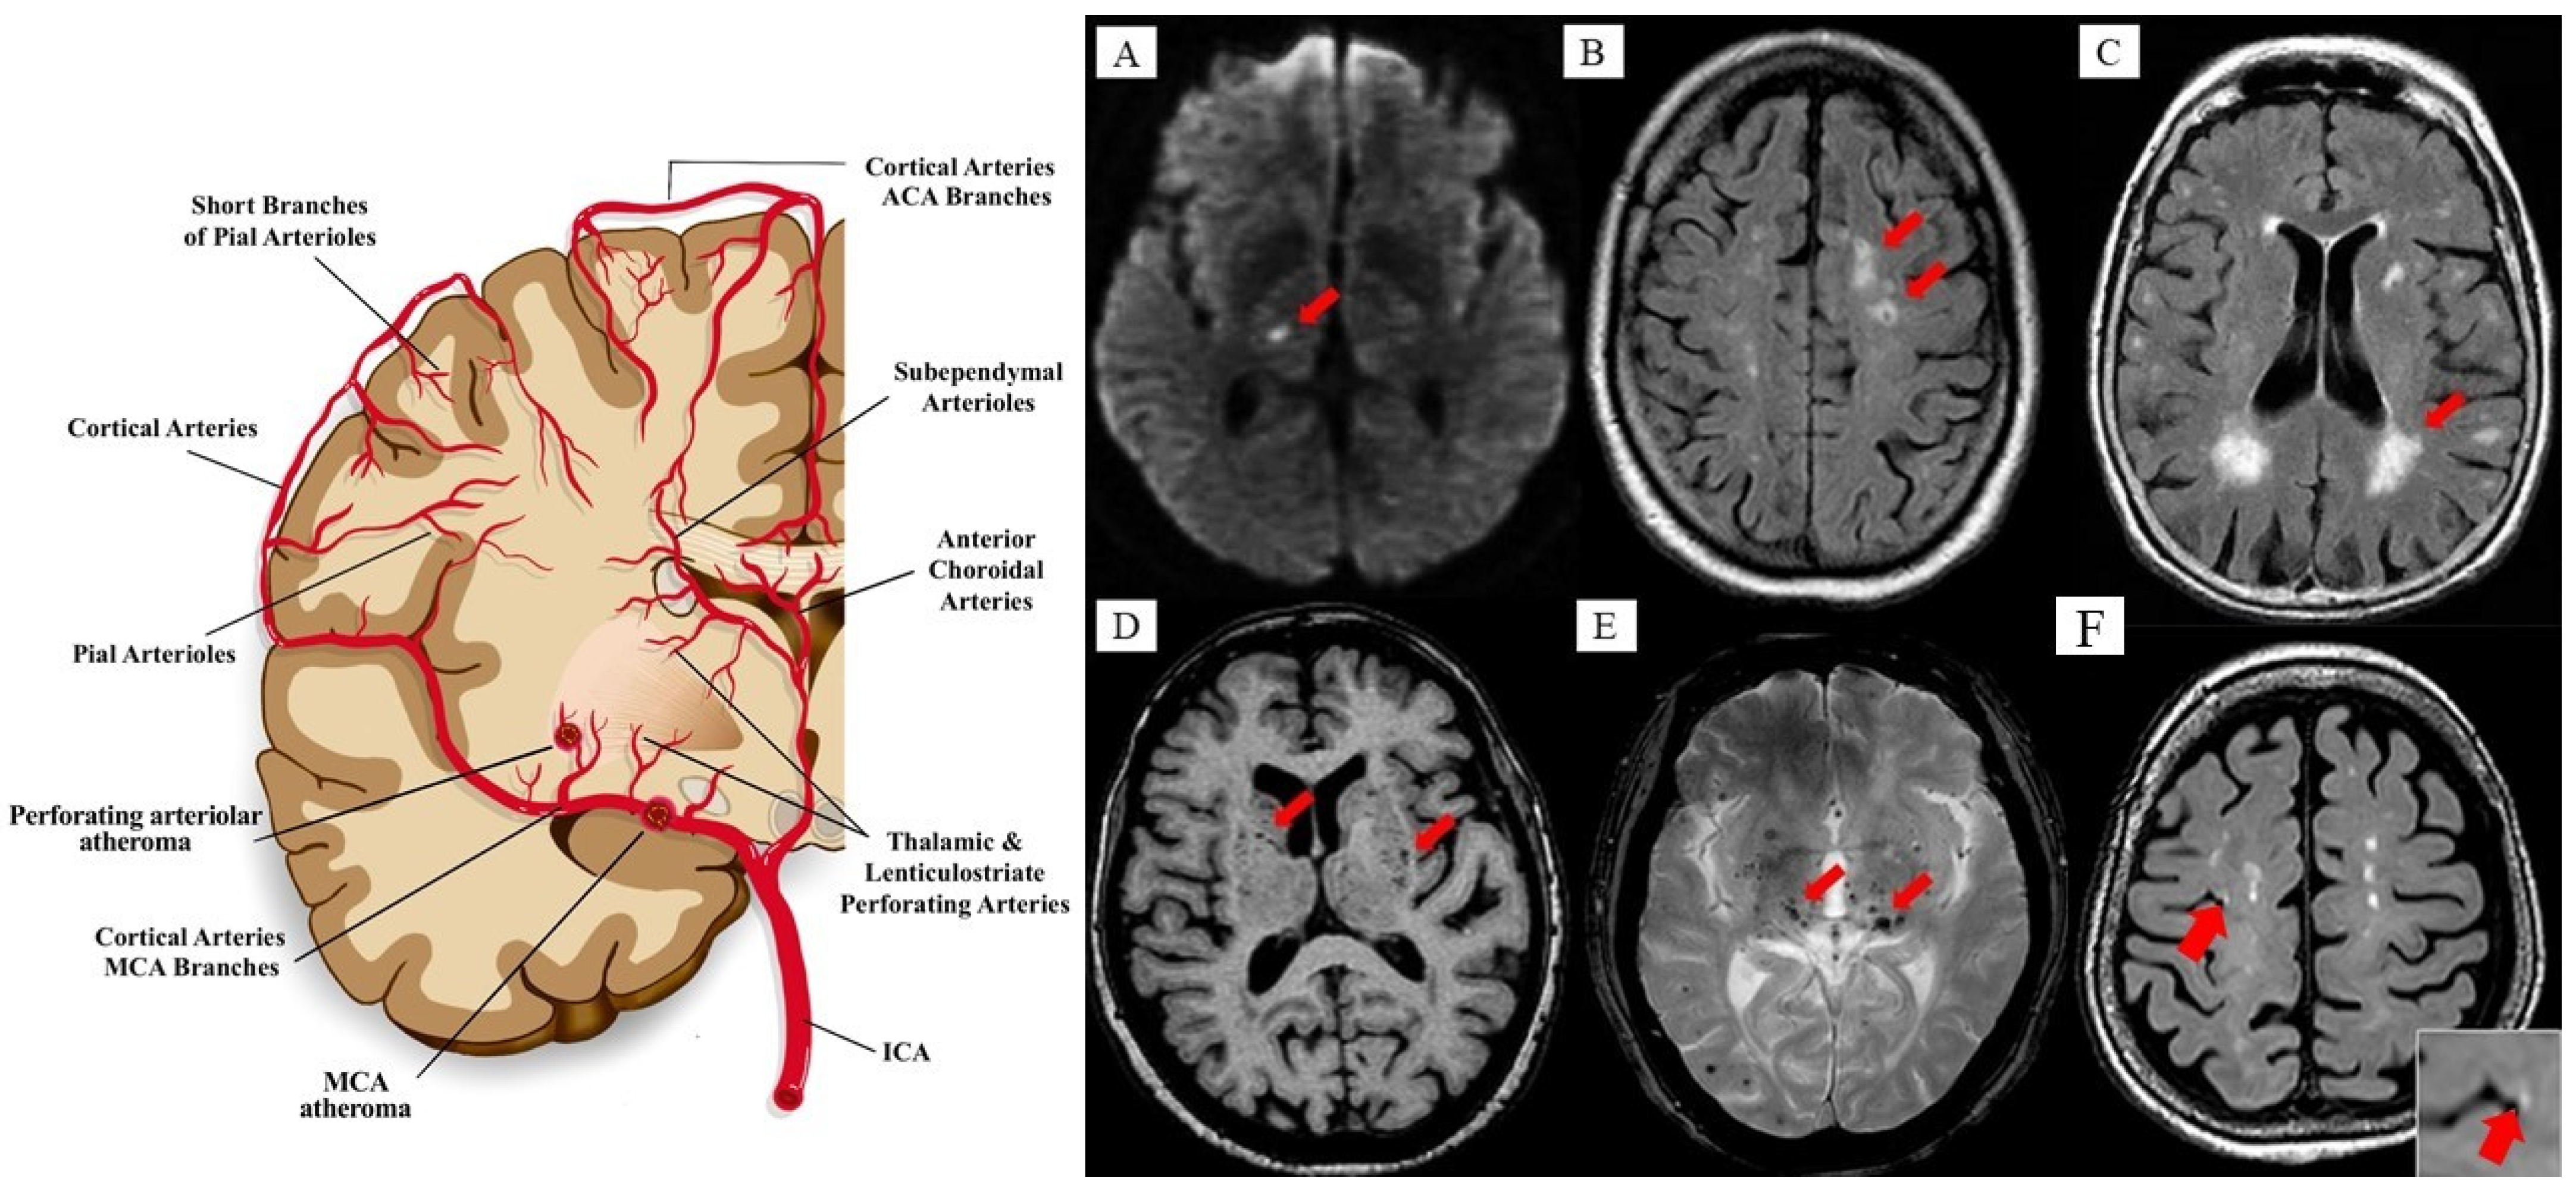

- Cuadrado-Godia, E.; Dwivedi, P.; Sharma, S.; Santiago, A.O.; Gonzalez, J.R.; Balcells, M.; Laird, J.; Turk, M.; Suri, H.S.; Nicolaides, A.; et al. Cerebral small vessel disease: A review focusing on pathophysiology, biomarkers, and machine learning strategies. J. Stroke 2018, 20, 302. [Google Scholar] [CrossRef]

- Li, Q.; Yang, Y.; Reis, C.; Tao, T.; Li, W.; Li, X.; Zhang, J.H. Cerebral small vessel disease. Cell Transplant. 2018, 27, 1711–1722. [Google Scholar] [CrossRef] [PubMed]

- Wardlaw, J.M.; Smith, C.; Dichgans, M. Small vessel disease: Mechanisms and clinical implications. Lancet Neurol. 2019, 18, 684–696. [Google Scholar] [CrossRef]

- Zwanenburg, J.J.; van Osch, M.J. Targeting cerebral small vessel disease with MRI. Stroke 2017, 48, 3175–3182. [Google Scholar] [CrossRef]

- Wardlaw, J.M.; Smith, E.E.; Biessels, G.J.; Cordonnier, C.; Fazekas, F.; Frayne, R.; Lindley, R.I.; O’Brien, J.T.; Barkhof, F.; Benavente, O.R.; et al. Standards for reporting vascular changes on neuroimaging (STRIVE v1): Neuroimaging standards for research into small vessel disease and its contribution to ageing and neurodegeneration. Lancet Neurol. 2013, 12, 822–838. [Google Scholar] [CrossRef]